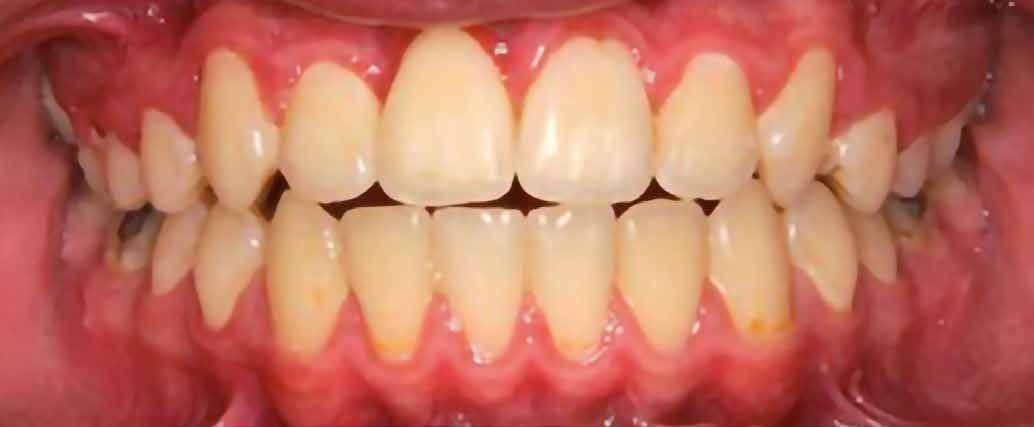

A szemfog oldalsó kismetsző helyére történő bemozgatása során a fog átalakítása javasolt a két fog eltérő morfológiai adottságai miatt (1. a-b. ábra). A fog kontúrozása, vagy úgynevezett formázása magába foglalja az approximális felszínek elcsiszolását, valamint a többi fogfelszín igazítását a kívánt fogformának megfelelően [1].

A kismetsző és szemfog klinikai koronái közötti eltérések a következőek: mezio-disztálisan keskenyebb oldalsó metsző, csücsök hiánya, egyenes éli lefutás, és a vesztibuláris felszín domborulata is kevésbé kifejezett [2,3]. A szemfoggal összehasonlítva, az oldalsó metsző rendszerint rövidebb és keskenyebb mind mezio-disztálisan, mind vesztibulo-orálisan. Az átformázott szemfog és az oldalsó metsző anatómiai alakja közötti egyezés függ az elülső zóna mint egység formájától is. Kataoke és Nishimura három alapformát határozott meg az elülső fogak tekintetében: négyszögletes, óvóid és háromszög formájú [4]. A frontfogak vesztibuláris felszínét a három kúp egységeként írják le (kúpos fejlődési mamelonok): meziális, disztális és centrális. A szemfogak esetén a három közül a központi a legdominánsabb, de nem ugyanez a helyzet az oldalsó metsző esetében. Háromszög alakú fogkorona esetén a meziális és disztális érvényesül jobban, négyszögletes formánál mindhárom egyenlő arányban domborodik, míg óvóid forma esetén a középső kerül túlsúlyba. Ennek megfelelően a szemfog csücskét el kell csiszolni, és kompozit felépítéssel az elülső anatómiai formához illő oldalsó metsző alakzatot kialakítani a szélső élek megfelelő hangsúlyozásával [5]. Amennyiben az elülső fogak formája háromszögletes, akkor kifejezett meziális és disztális felépítésekre lesz szükség. Négyszögletes forma esetén a szemfog meglévő centrális kúposságát kiegyensúlyozva építik fel a fogat. Az elülső fogak ovoid alakzata esetén a meziális és disztális kúposságot alig vagy egyáltalán nem hangsúlyozzák

1. a–b ábra

(amennyiben a szemfog formája csiszolás után megegyezik az oldalsó metszőfog kívánt alakjával). A szemfogaktól eltérően az oldalsó metszők palatinális felszíne konkáv mind mezio-disztális, mind apikokoronális irányban [6].